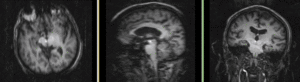

RegLib C14 unregistered.png MRI and PET before registration (click to enlarge)

RegLib C14 registered.gif MRI and PET after registration (click to enlarge)